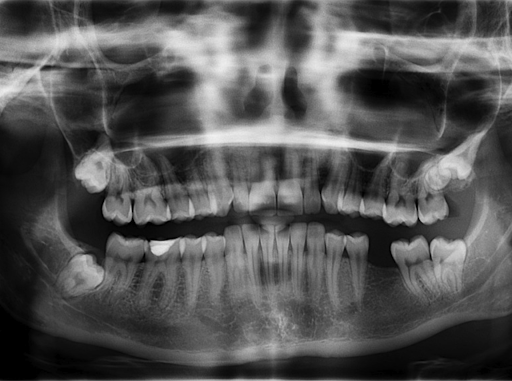

Panorex, also known as panoramic X-ray, is a dental imaging technique that provides a two-dimensional view of the entire mouth, including the teeth, jaws, sinuses, and nasal cavities. We use it to assess the overall health of the teeth and jaws, and detect any impacted teeth, wisdom teeth, cysts, tumors or fractures. It can also evaluate the alignment of the teeth and jaws. visit our website to learn more about Panorex and other dental services.